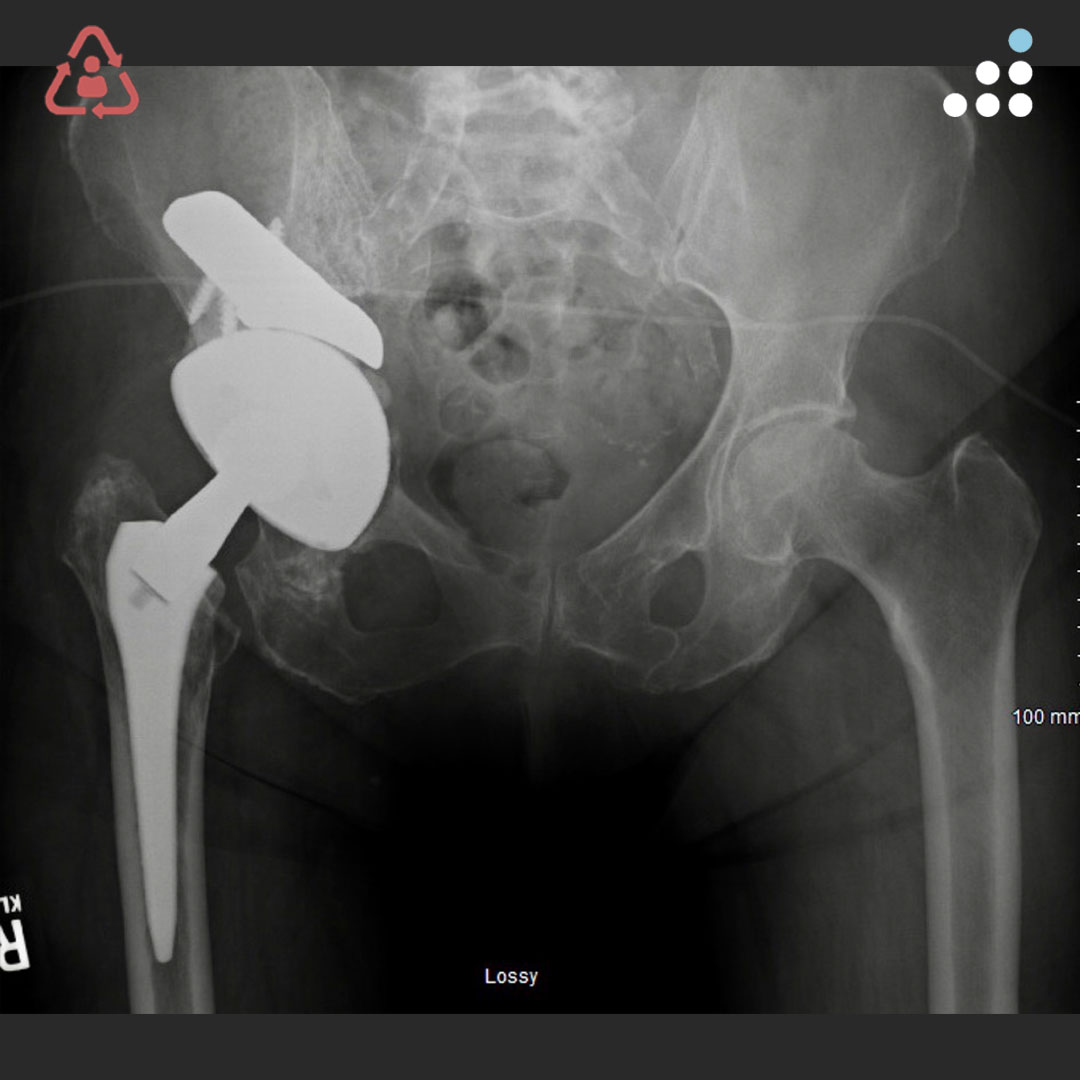

From buyxraysonline.com

GUNSHOT Gunshot Orthobullets Gun shot wounds are high energy injuries that contribute to extensive soft tissue damage and. Wound ≤1 cm, minimal contamination or muscle damage. in the current review, the authors point out key aspects and principles requiring attention when treating low energy. a gunshot wound (gsw) is a penetrating injury caused by a projectile (e.g. there is a. Gunshot Orthobullets.